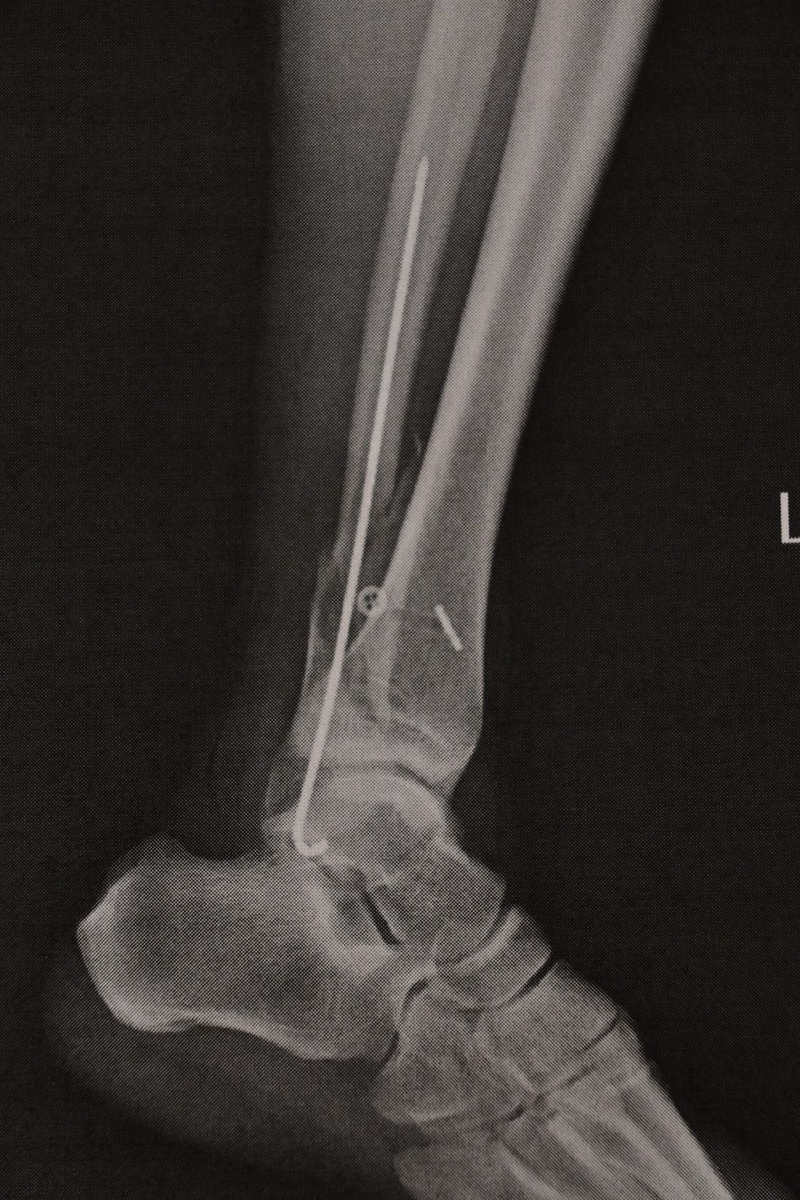

一昨日深夜の手術終了時に手術したお医者さんに藁半紙でX線写真をもらいました。

紙を撮影してるので意味ありませんが

腓骨の中に金属棒を入れての処置になったそうです。プレートでの固定は切開部が大きく術後の痛みが大きい、プレート取り外し時の入院が長くなるので金属棒でよかったです。

横に見える貫通穴は筋が切断したので人工のものを設置した穴です。

もう一か所、縫い合わせた筋がありますが画像で確認できません。

結論として切開が少なくピン抜きも楽な形にまとめてもらいました。切開部分が多いと手術後の痛みが激しいので切開が少なくてよかったです。